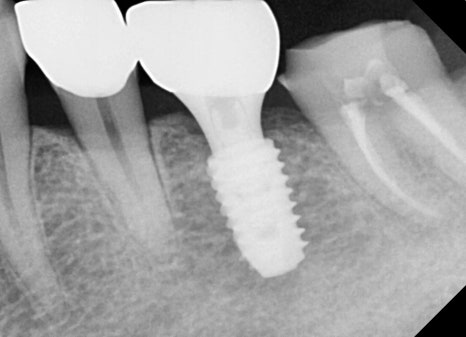

Right photo: Partial X-ray showing the treated tooth after root canal treatment and the implant well positioned.

➡ The tooth that received root canal treatment was properly filled all the way to the root with medication, and a prosthesis (crown) was placed well on top.

➡ The missing molar was also functionally restored with an implant, and the patient was satisfied with both chewing strength and comfort.